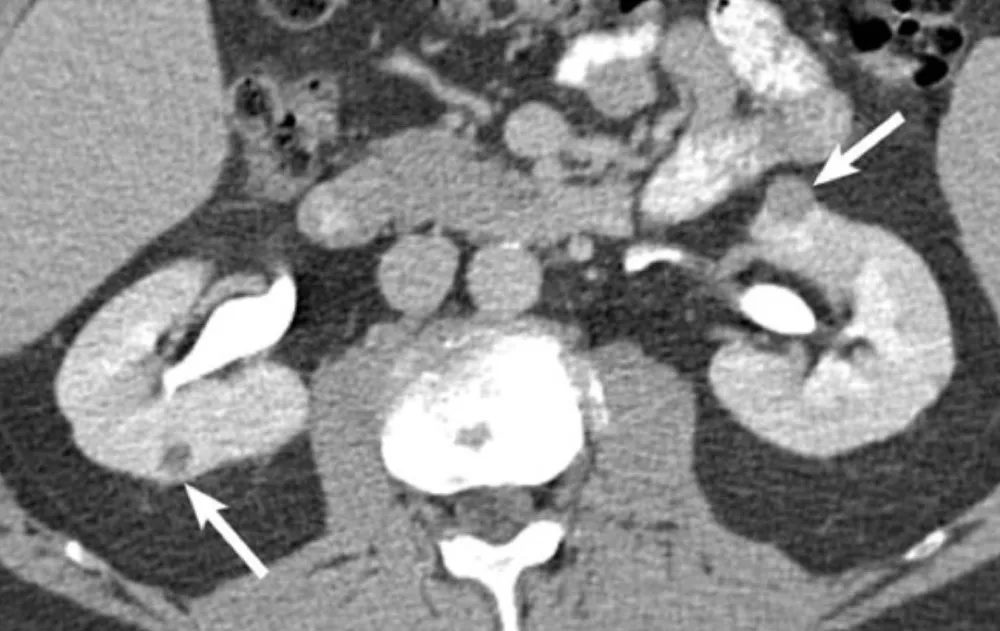

IRA + Icterícia: Um Caso que Exige Investigação Detalhada